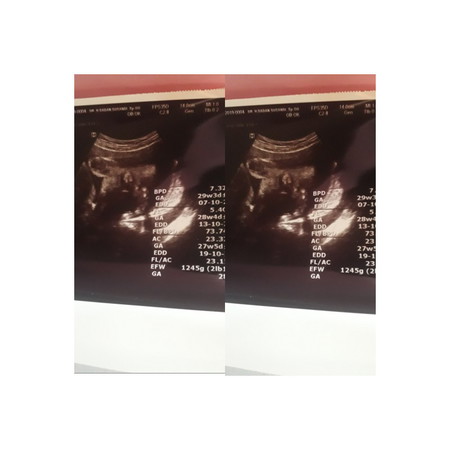

Salam bun, ini hasil USG aku kemarin UK 30week tapi bbj janinnya baru 1250g kira2 itu normal gk yaa bun, aku jadi worry takut kekecilan nnti pas lahiran Yg udah pengalaman cerita2 dikit dong pengalamannya?

Sama Bun q juga 30w 1240 gram.... Kata dokternya kecil.... Tapi klw baca artikel² sih normal nya 30w antara 1200-1300 bun....brarti kan msh normal ya... tapi dokternya bilang kecil jadi worry deh...

Masya allah kemarin aku juga usg bund bb janin juga 1,2 dan kata dokter normal karna di usia 30w batas bb janin itu 1,5 bund begitu kmarin bilngnya